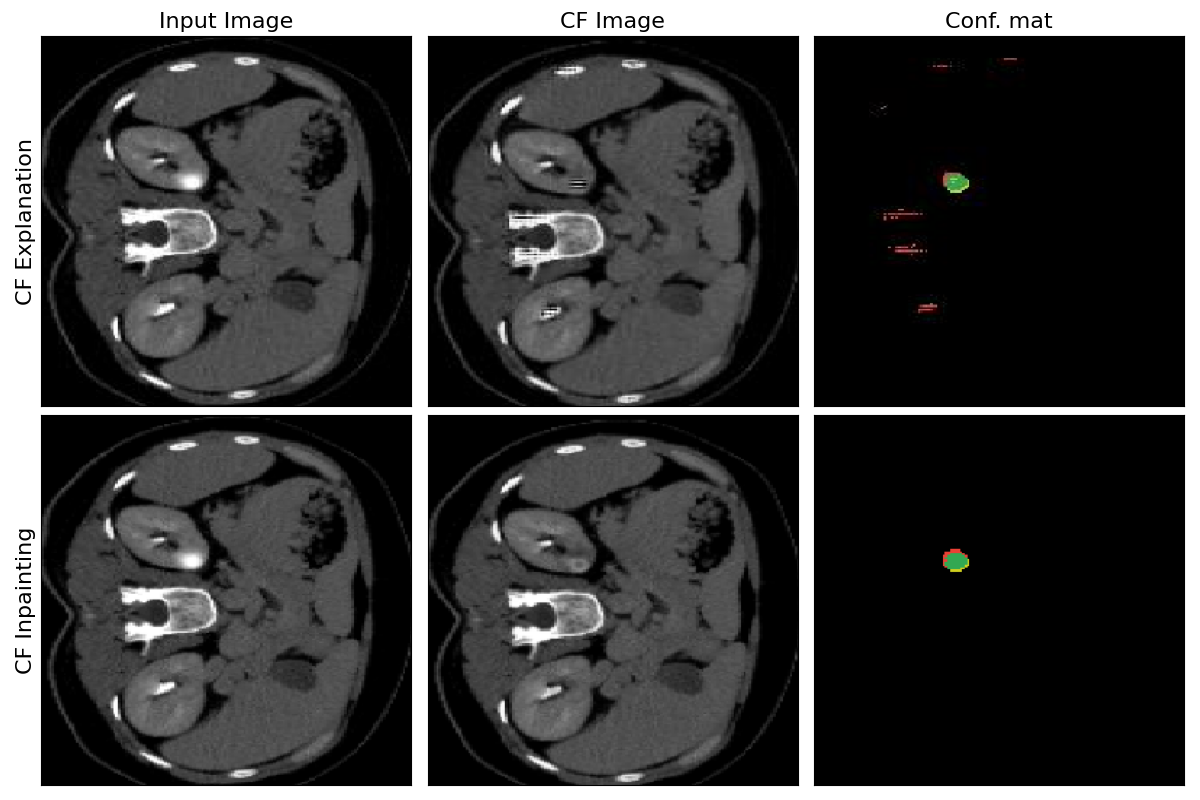

Refer to caption

Figure 6: Examples of images generated with perturbation-based Singla et al.* method equipped with skip connections and with the proposed counterfactual inpainting approach.

This experiment proves that the proposed counterfactual inpainting pipeline outperforms the base counterfactual explanation approach. Both methods are trained and evaluated in terms of segmentation accuracy for the extracted weak segmentation labels from the counterfactual images.

The benefits of using the counterfactual inpainting are two-fold. First, it does not require segmentation masks for enforcing local consistency. Second, the IoU score is much higher due to the fact that the model is simplified to only either inpaint the anomaly or not to produce the segmentation mask. Figure 6 gives qualitative evaluation of the generated counterfactuals following the two approaches.